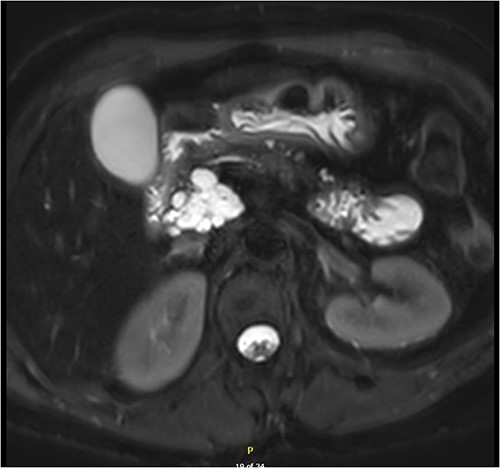

Magnetic resonance imaging (MRI) revealed a 6.9 cm multi-lobulated cystic pancreatic head lesion with underlying background changes of alcohol-related chronic pancreatitis. There was no biliary or pancreatic duct dilation, or other suspicious features for malignancy (Fig. 1). This lesion was thought to be a serous cystadenoma or pancreatic pseudocyst. Endoscopic ultrasound (EUS) revealed innumerable small cysts consistent with serous cystadenoma and fine-needle biopsy demonstrated benign ductal epithelium.

Multi-loculated head of pancreas cyst, with no pancreatic duct dilation.